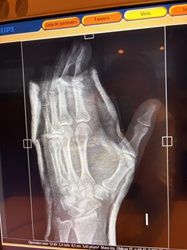

Fractura de falange producida por un anillo